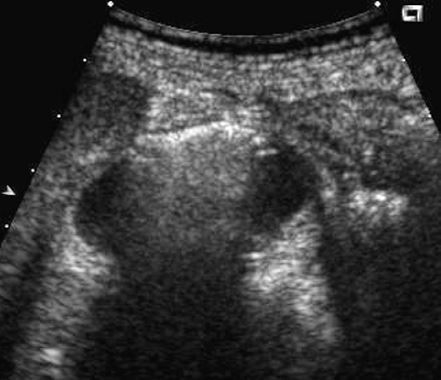

Gangrenous cholecystitis

• focal mucosal ulceration

• a focal bulge in the gallbladder wall.

• This is likely due to the combined effects of progressive increase in intraluminal pressure and focal weakening of the gallbladder wall

• patients will often have NEGATIVE Murphy’s sign